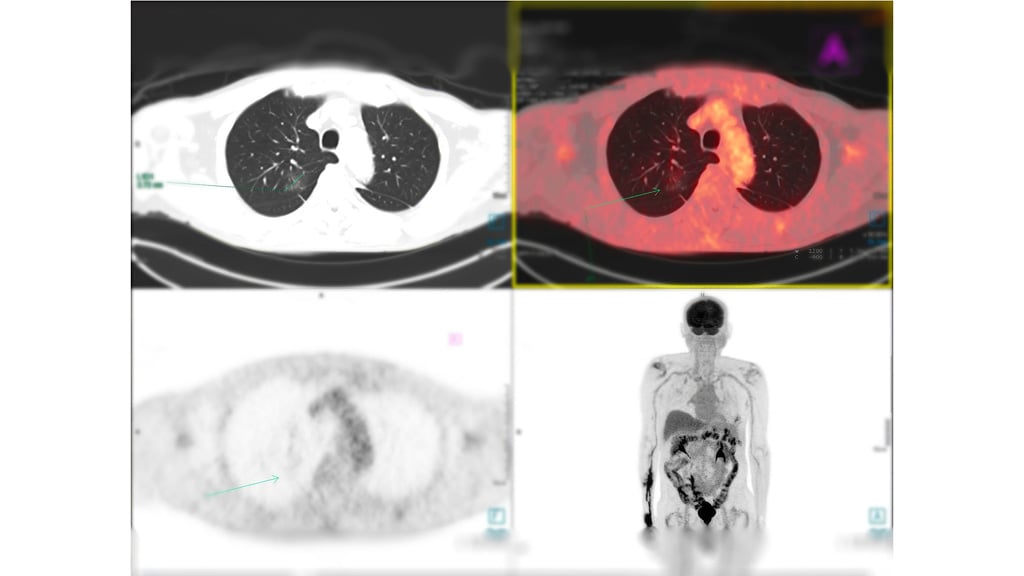

With more than 100+ years' experience, Curium is leveraging its expertise to help transform the treatment landscape with a robust precision theranostics pipeline.

Curium’s purpose is firmly built around patients, caregivers, and healthcare professionals. For more than 30 years, we’ve supported the neuroendocrine tumor (NET) community, not only with the first somatostatin receptor (SSTR) imaging for NETs, but also through advocacy and education.

As we bring our expertise to therapeutics, our purpose remains the same—to advance solutions through deep commitment, meaningful partnerships, and relentless focus on improving outcomes.